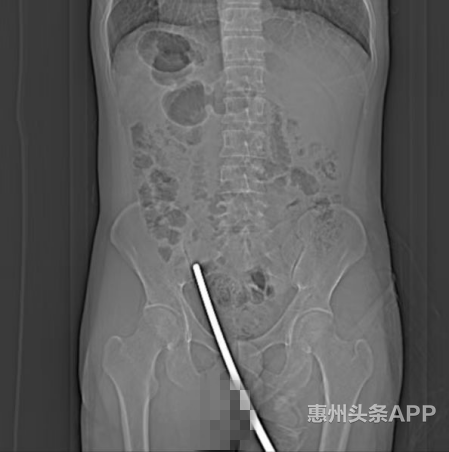

通过CT检查可见,钢管从会阴部位直入小腹部,所幸刺入的钢管未伤及重要脏器和部位,但为进一步确定钢管对腹内肝、胆、胃、肠等等的损伤情况,尽快帮助患者移除刺在臀部腹部的钢管,消除危险,减轻痛苦,医院创伤中心多学科会诊确定手术方案后,立即走绿色通道将患者直接送入手术室。

钢管从会阴部位直入小腹部,所幸刺入的钢管未伤及重要脏器和部位。